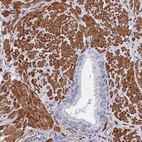

Immunohistochemical staining of human placenta shows strong membranous positivity in trophoblastic cells.